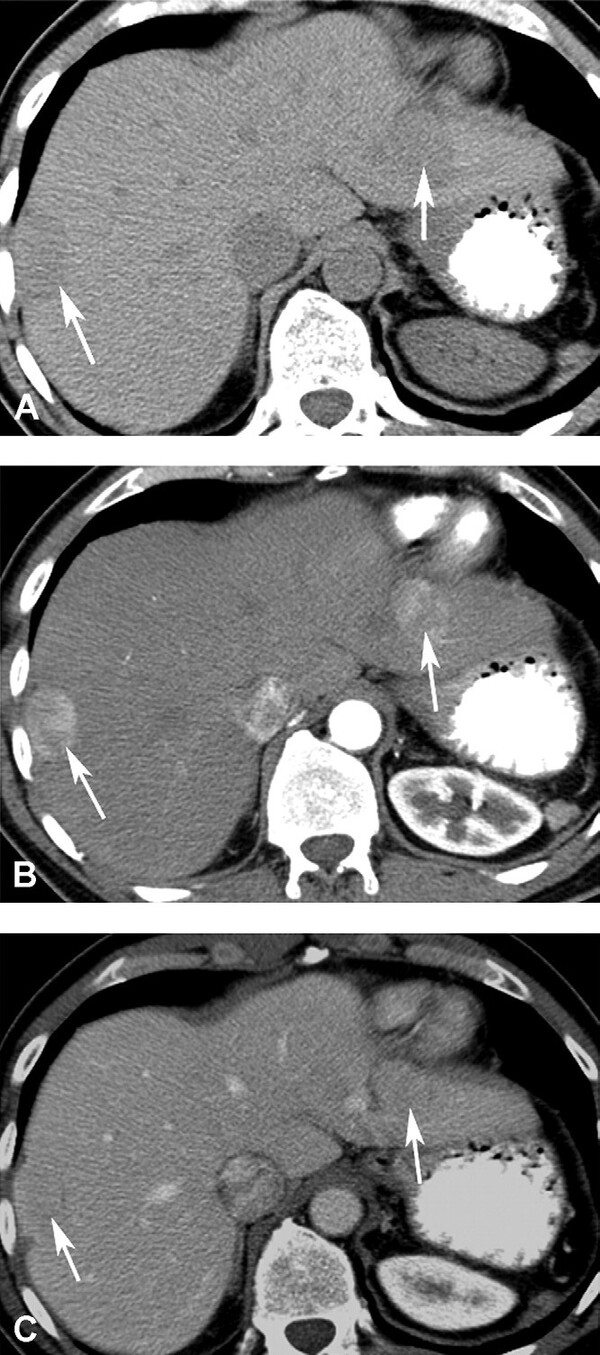

Hình 4. Hemangioma khổng lồ ở bệnh nhân nữ 42 tuổi. (A) CT thì động mạch thấy bắt quang dạng nốt ngoại vi (mũi tên). (B) thì tĩnh mạch ửa thấy nốt bắt quang tăng lên (mũi tên). (C). Bắt quang vẫn giữ nguyên như vậy ở thì muộn (mũi tên) với không lấp đầy thuốc do huyết khối và hoại tử mạnh.

Hình 5. Hemangioma khổng lồ. Tổn thương giảm tín hiệu (mũi tên) trên hình T1W 3D GRE (A) và tăng tín hiệu (mũ I tên) kèm vùng nang ở trung tâm (đầu mũi tên) trên hình T2W SSFSE (B). Có bắt quang dạng nốt ngoại vi không kề nhau (mũi tên) ở thì ộng mạch (C), sau đó khuynh hướng lấp vào trung tâm hợp lưu (mũi tên) ở thì tĩnh mạch cửa (D). Tu y nhiên, không lấp đầy thuốc tương phản hoàn toàn (mũi tên ) ở thì muộn hình axial (E) và coronal (F).